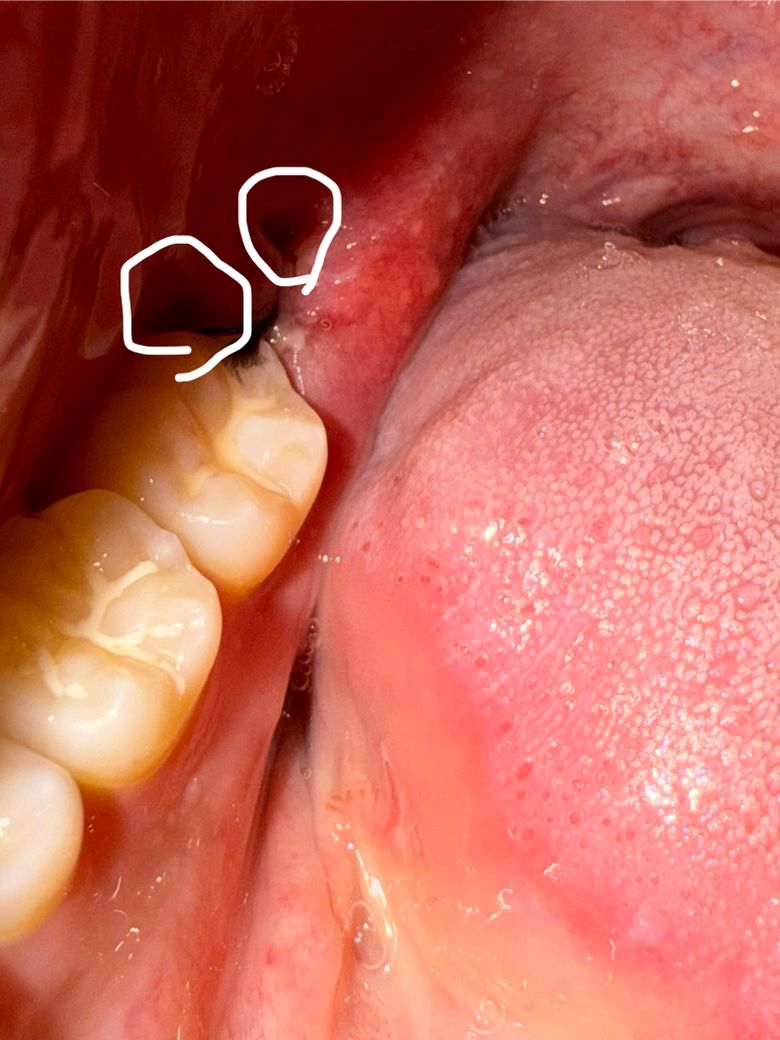

사랑니 발치 후 3일차인데 괜찮은건가요??

흰색으로 동그라미 친 부분에 구멍 같은게 보이고 실밥도 하나가 풀렸습니다… 얼굴 붓기는 더 붓고 통증은 아주 실짝 있네요. 혹시 드라이소캣이나 문제가 있는거일까요?..(원본 사진도 첨부합니다!)

사진상 잇몸은 어느정도 잘 낫고 있습니다 너무 걱정하지 마시고 발치 후 주의사항 잘 지키시기 바랍니다

사진으로 봤을 경우에는 발치한 부위가 잘 아물고 있는 것으로 보입니다. 너무 걱정하지 않으셔도 될 것으로 생각됩니다. 사랑니를 발치한 부위는 자극되지 않는 것이 좋습니다. 자극이 된다면 출혈이 되고 치유가 늦어질 수 있기 때문입니다.

-> 문제는 없어보이고 잘 낫고 있는 것 같습니다.

아직 잇몸상처나 붓기가 다 가라 앉지 않아서 그러는거니 너무 걱정하지 않으셔도 될것같습니다.